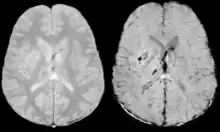

Diffusion weighted imaging offers a powerful means to detect acute stroke. Although it is well known that gradient echo imaging can detect hemorrhage, it is best detected with SWI. In the example shown here, the gradient echo image shows the region of likely cytotoxic edema whereas the SW image shows the likely localization of the stroke and the vascular territory affected (data acquired at 1.5 T).

The bright region in the gradient echo weighted image shows the area affected in this acute stroke example. The arrows in the SWI image may show the tissue at risk that has been affected by the stroke (A, B, C) and the location of the stroke itself (D). The reason that we are able to see the affected vascular territory could be because there is a reduced level of oxygen saturation in this tissue, suggesting that the flow to this region of the brain could be reduced post stroke. Another possible explanation is that there is an increase in local venous blood volume. In either case, this image suggests that the tissue associated with this vascular territory could be tissue at risk. Future stroke research will involve comparisons of perfusion weighted imaging and SWI to learn more about local flow and oxygen saturation.